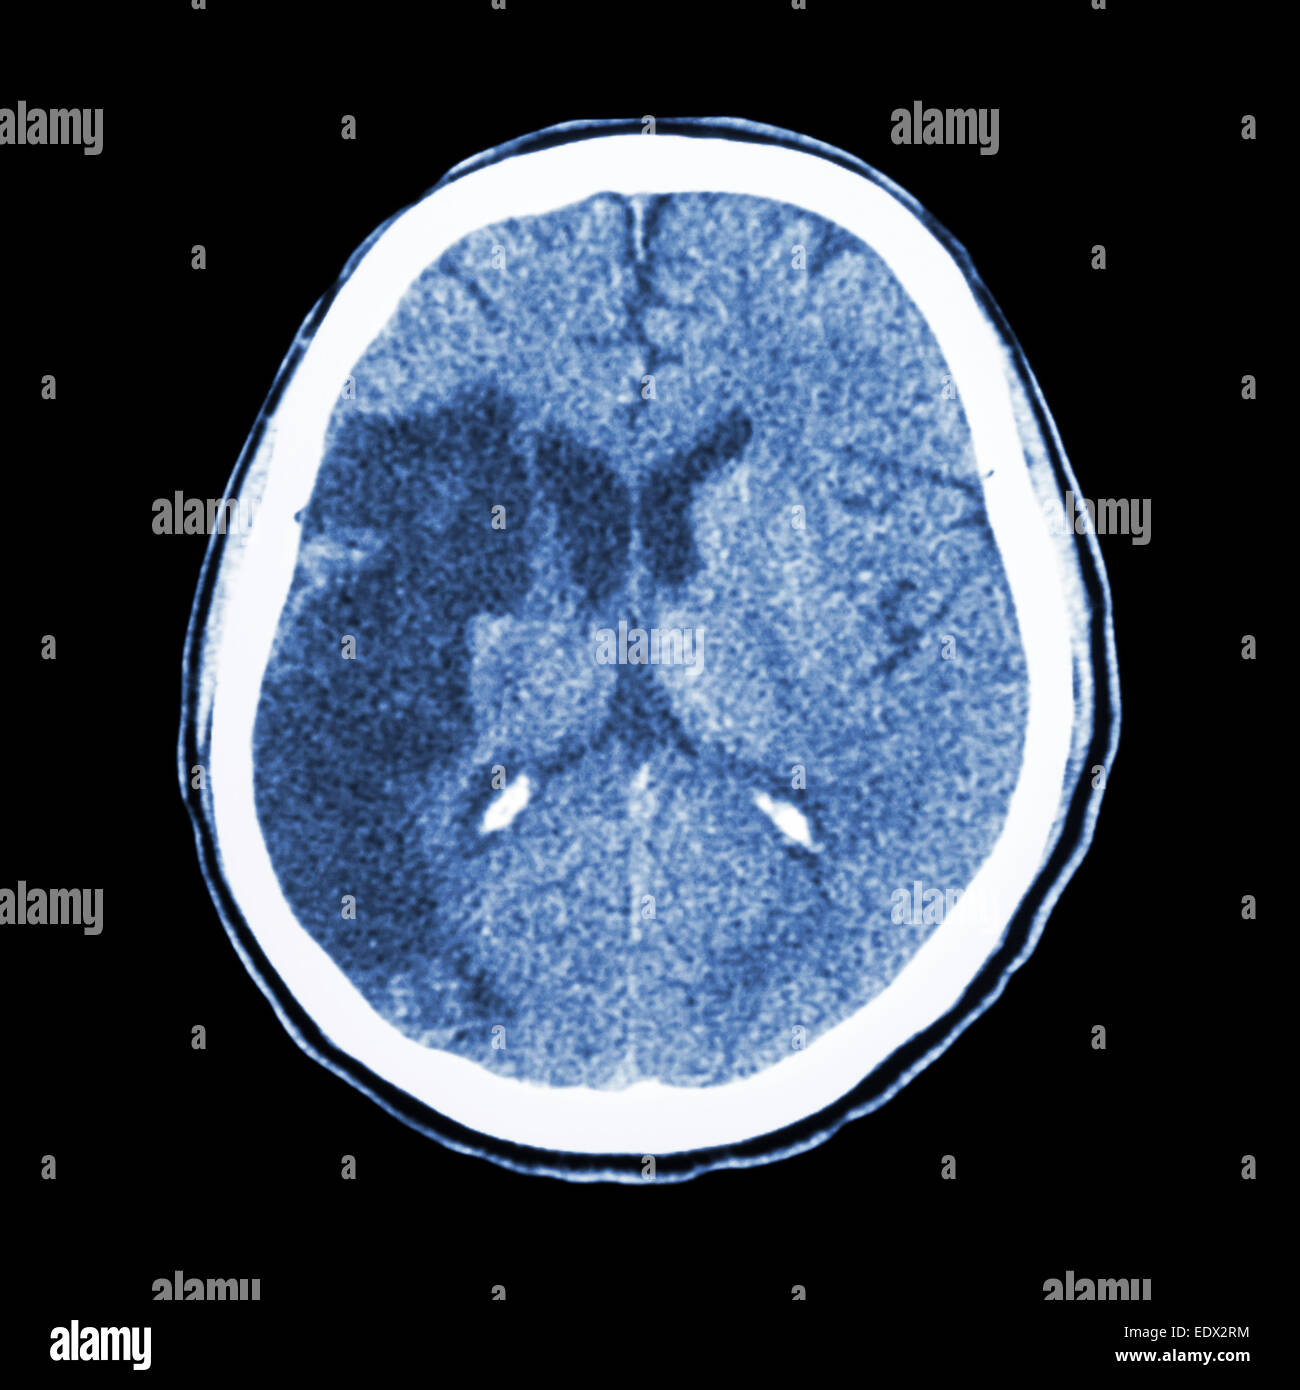

CT scan d'un vieil homme de 84 ans souffrant de la maladie d'Alzheimer. La TDM montre l'atrophie du cerveau. Banque D'Imageshttps://www.alamyimages.fr/image-license-details/?v=1https://www.alamyimages.fr/photo-image-ct-scan-d-un-vieil-homme-de-84-ans-souffrant-de-la-maladie-d-alzheimer-la-tdm-montre-l-atrophie-du-cerveau-84989410.html

CT scan d'un vieil homme de 84 ans souffrant de la maladie d'Alzheimer. La TDM montre l'atrophie du cerveau. Banque D'Imageshttps://www.alamyimages.fr/image-license-details/?v=1https://www.alamyimages.fr/photo-image-ct-scan-d-un-vieil-homme-de-84-ans-souffrant-de-la-maladie-d-alzheimer-la-tdm-montre-l-atrophie-du-cerveau-84989410.htmlRMEX7GT2–CT scan d'un vieil homme de 84 ans souffrant de la maladie d'Alzheimer. La TDM montre l'atrophie du cerveau.